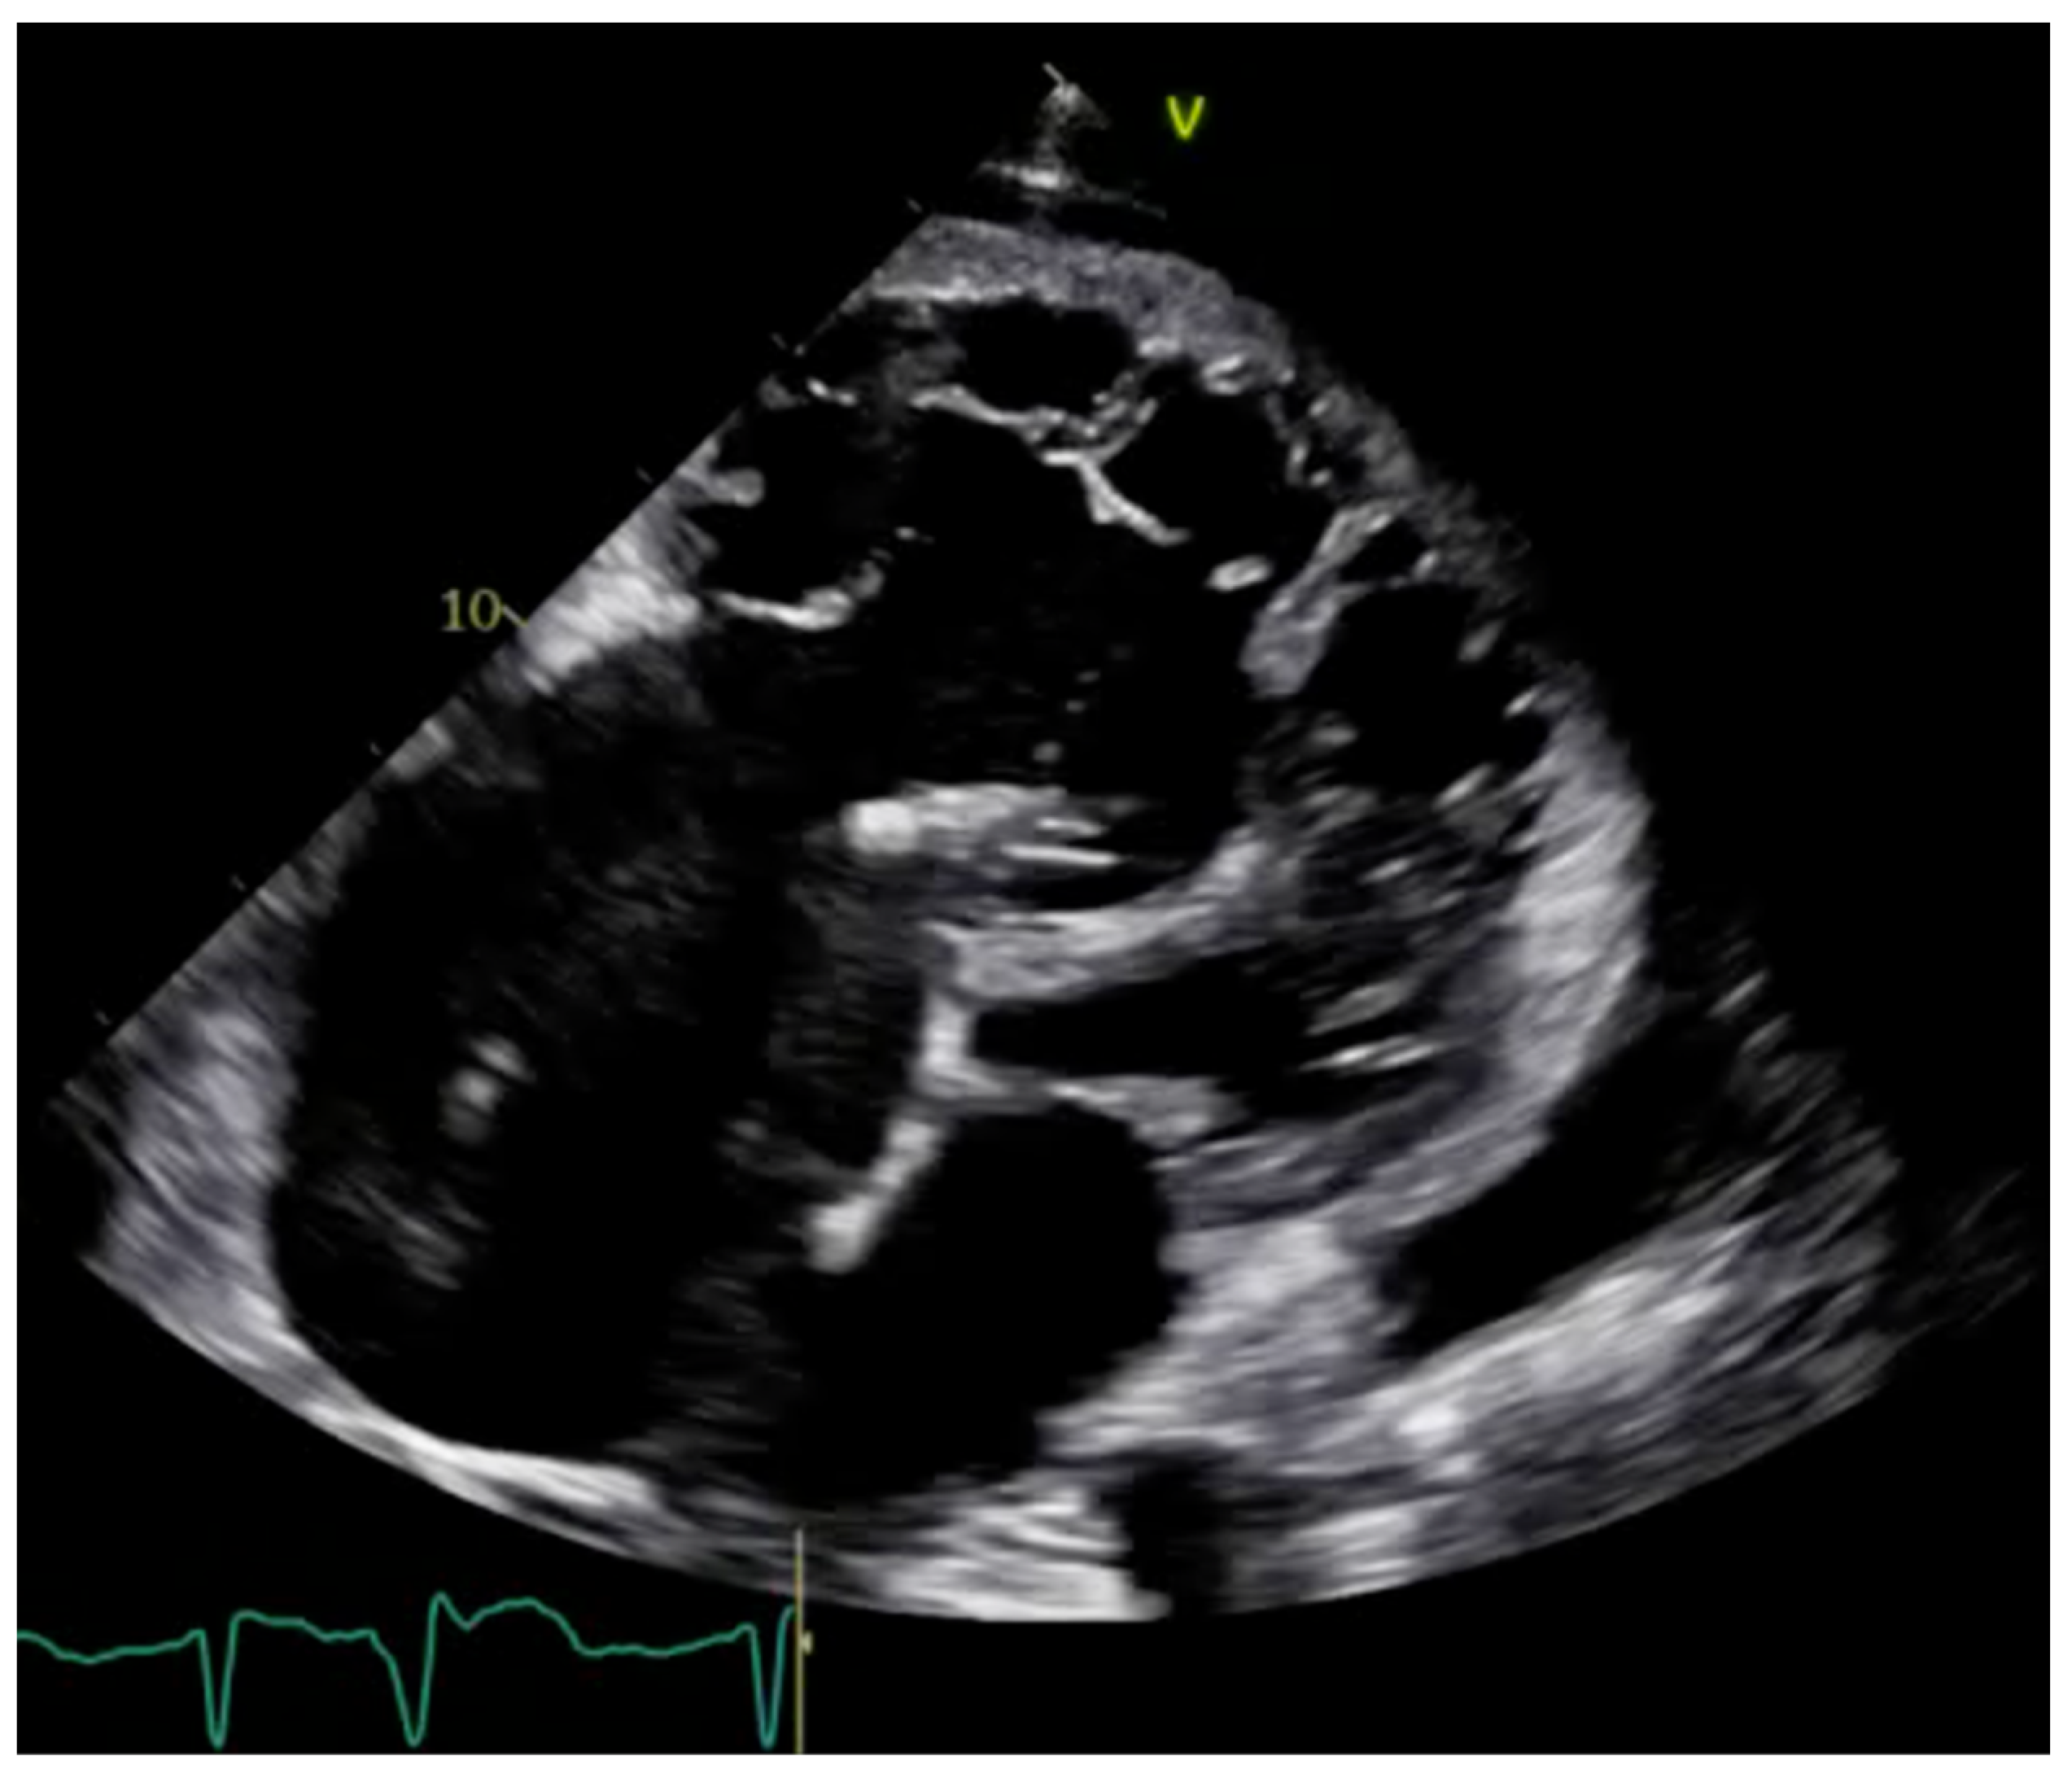

2.1. Echocardiography: The First Line of Diagnosis

5.1. Hypertrophic Cardiomyopathy